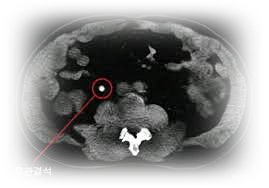

이러한 결석은 보통 신장에서 발생합니다.

신장, 요도, 방광, 요도 등에 있습니다

문제를 일으키고 있어요.